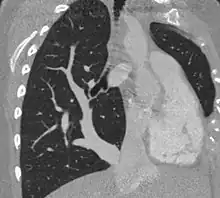

| Scimitar syndrome chest CT | |

The diagnosis is made by transthoracic or transesophageal echocardiography and selective pulmonary angiography.[5] More recently by CT angiography or MR Angiography.

Pulmonary angiography demonstrates anomalous arterial supply to right lower lobe.[5]